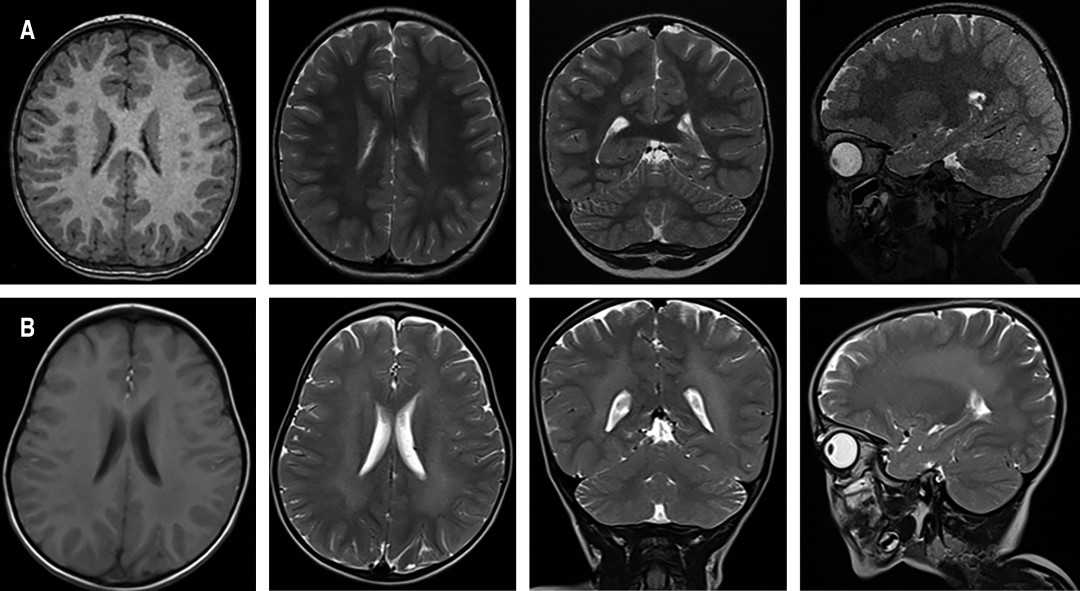

En una RMC realizada siete meses después de la primera, se observó alteración de la intensidad de la señal en la sustancia blanca con hiperintensidad en T2 e hipointensidad en T1 (Figura 1), sugestivas de desmielinización. Aunque fue considerada como una variante de LDM de inicio infantil tardío, su comportamiento clínico no cumplió con los criterios recomendados para trasplante de médula ósea, por lo cual solo recibió cuidados paliativos y terapia de rehabilitación.

En los estudios de RMC suele encontrarse hiperintensidad confluente y simétrica en FLAIR de forma difusa en la sustancia blanca periventricular frontal y parietal, con imágenes hipointensas en T1, compatibles con desmielinización.20 Pero, como sucedió con nuestro paciente en su primera RMC, es posible encontrar una neuroimagen normal en estadios iniciales. La alteración en la mielina puede ser establecida con la medición de la velocidad de neuroconducción por electromiografía, donde se observa un patrón de polineuropatía desmielinizante, hallazgo observado en este paciente. Otros estudios recomendados son la ecografía o la tomografía de abdomen, los cuales pueden revelar pólipos vesiculares hiperplásicos asociados al desarrollo de carcinoma de vesícula biliar (no visualizado en el presente caso).21

Figura 1